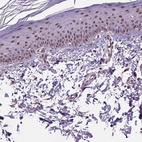

Immunohistochemistry analysis in human skin and pancreas tissues using Anti-UBA3 antibody. Corresponding UBA3 RNA-seq data are presented for the same tissues.